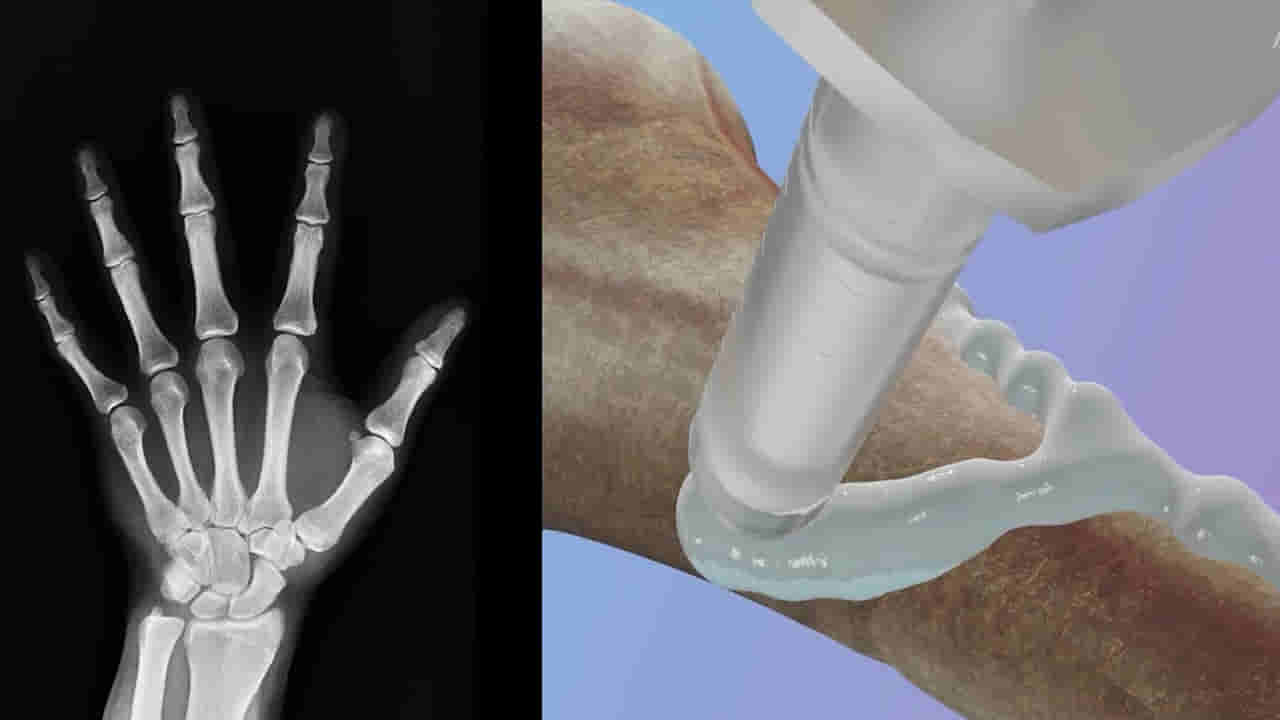

ఆధునిక వైద్య విజ్ఞాన శాస్త్రం కొత్తపుంతలు తొక్కుతోంది. ఎన్నో అధ్యయనాలు, సాంకేతిక పరిణామాలతో అసాధ్యాన్ని సుసాధ్యం చేస్తోంది.. వైద్య శాస్త్రం అభివృద్ధి నానాటికి పెరుగుతుండటంతో అన్ని రకాల వ్యాధులకు చికిత్స సులభం అవుతోంది.. ప్రజా ఆరోగ్యాన్ని కాపాడేందుకు ఎన్నో పరిశోధనలు అందుబాటులోకి వస్తున్నాయి. తాజాగా.. చైనా పరిశోధకులు.. సరికొత్త ఆవిష్కరణను ప్రపంచానికి పరిచయం చేశారు. పగుళ్లు, విరిగిన ఎముక ముక్కలను కేవలం మూడు నిమిషాల్లో చికిత్స చేయడానికి ఉపయోగపడే ఎముక జిగురు(Bone Glue) ను చైనా పరిశోధకులు అభివృద్ధి చేశారు. ఎముకల పగుళ్లను సరిచేయడానికి, అలాగే ఆర్థోపెడిక్ పరికరాలను అతికించడానికి ఎముక అంటుకునే జిగురు చాలా కాలంగా అవసరమైన పదార్థంగా పరిగణిస్తున్నారు. కానీ చైనా శాస్త్రవేత్తలు అసలైన ఈ జిగురు పదార్థం కోడ్ను ఛేదించినట్లు కనిపిస్తోంది.

మిస్టర్ లిన్ ప్రకారం.. రక్తం అధికంగా ఉండే వాతావరణంలో కూడా, ఈ అంటుకునే పదార్థం రెండు నుండి మూడు నిమిషాల్లోనే ఖచ్చితమైన స్థిరీకరణను సాధించగలదు. ఎముక నయం అయినప్పుడు ఈ జిగురు శరీరం సహజంగా గ్రహించగలదు.. ఇంప్లాంట్లను తొలగించడానికి మరొక శస్త్రచికిత్స అవసరం లేకుండా చేస్తుంది.

“బోన్-02” భద్రత – ప్రభావ ప్రమాణాలు రెండింటిలోనూ మంచి పనితీరును ప్రదర్శించిందని ప్రయోగశాల పరీక్షలు నిర్ధారించాయి. ఒక ట్రయల్లో, ఈ ప్రక్రియ 180 సెకన్లు లేదా మూడు నిమిషాల కంటే తక్కువ సమయంలో పూర్తయింది.. అయితే సాంప్రదాయ చికిత్సా పద్ధతులకు స్టీల్ ప్లేట్లు, స్క్రూలను అమర్చడానికి పెద్ద కోత అవసరం. CCTV ప్రకారం , 150 మందికి పైగా రోగులలో ఎముక జిగురును విజయవంతంగా పరీక్షించారు..

అతుక్కొని ఉన్న ఎముకలు గరిష్టంగా 400 పౌండ్లకు పైగా బంధన శక్తిని, దాదాపు 0.5 MPa కోత బలాన్ని, దాదాపు 10 MPa సంపీడన బలాన్ని చూపించాయి.. ఇది ఉత్పత్తి సాంప్రదాయ మెటల్ ఇంప్లాంట్లను భర్తీ చేయగల సామర్థ్యాన్ని కలిగి ఉండవచ్చని హైలైట్ చేస్తుంది. ఇది ప్రతిచర్య, సంక్రమణ ప్రమాదాలను కూడా తగ్గించగలదని శాస్త్రవేత్తలు పేర్కొన్నారు.